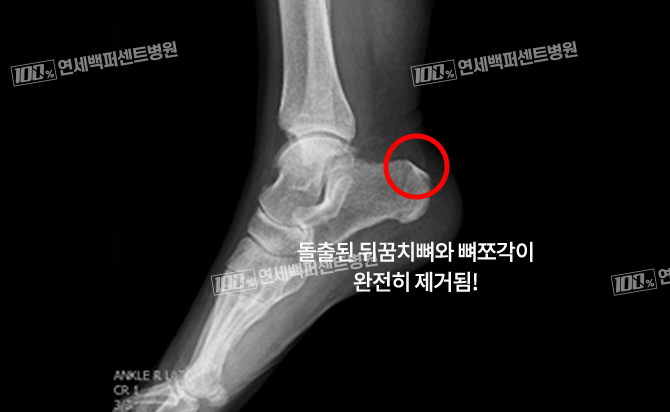

최소침습 해글런드 변형 절제술

긴 절개 없이 최소침습으로 치료!

돌출된 뒤꿈치 뼈와 아킬레스건 염증 동시 치료!

수 차례의 충격파 치료, 주사치료에 반응 없는 난치성 아킬레스건염 해결!

손OO (23.01.09)

손OO (23.03.09)